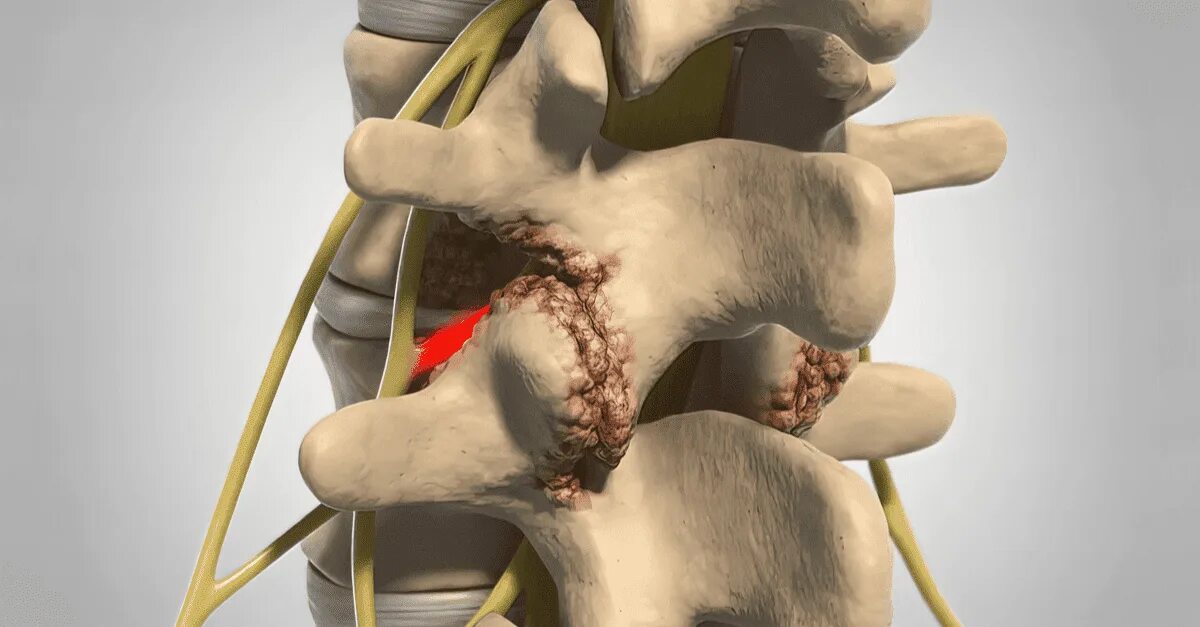

Артроз фасеточных суставов позвоночника